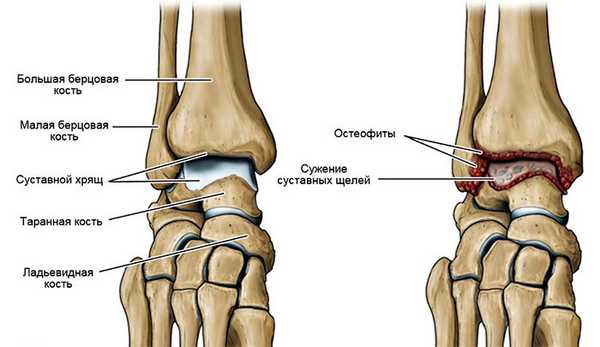

Слева - схематическое изображение строение нармального голеностопного сустава,

Справа - разрушение сустава из-за артроза.

Как и любой сустав человеческого организма, голеностопное соединение снабжено хрящевыми прослойками. Они уменьшают трение, обеспечивают амортизирующую функцию. Если в хрящах развивается воспалительный процесс, сопровождающийся постепенной дегенерацией и разрушением тканей, говорят о развитии артроза голеностопного сустава.

Постепенное истончение хрящевой ткани повышает нагрузку на кости. Со временем, когда хрящ перестает защищать костные ткани, начинается деформация пораженного заболеванием сустава.